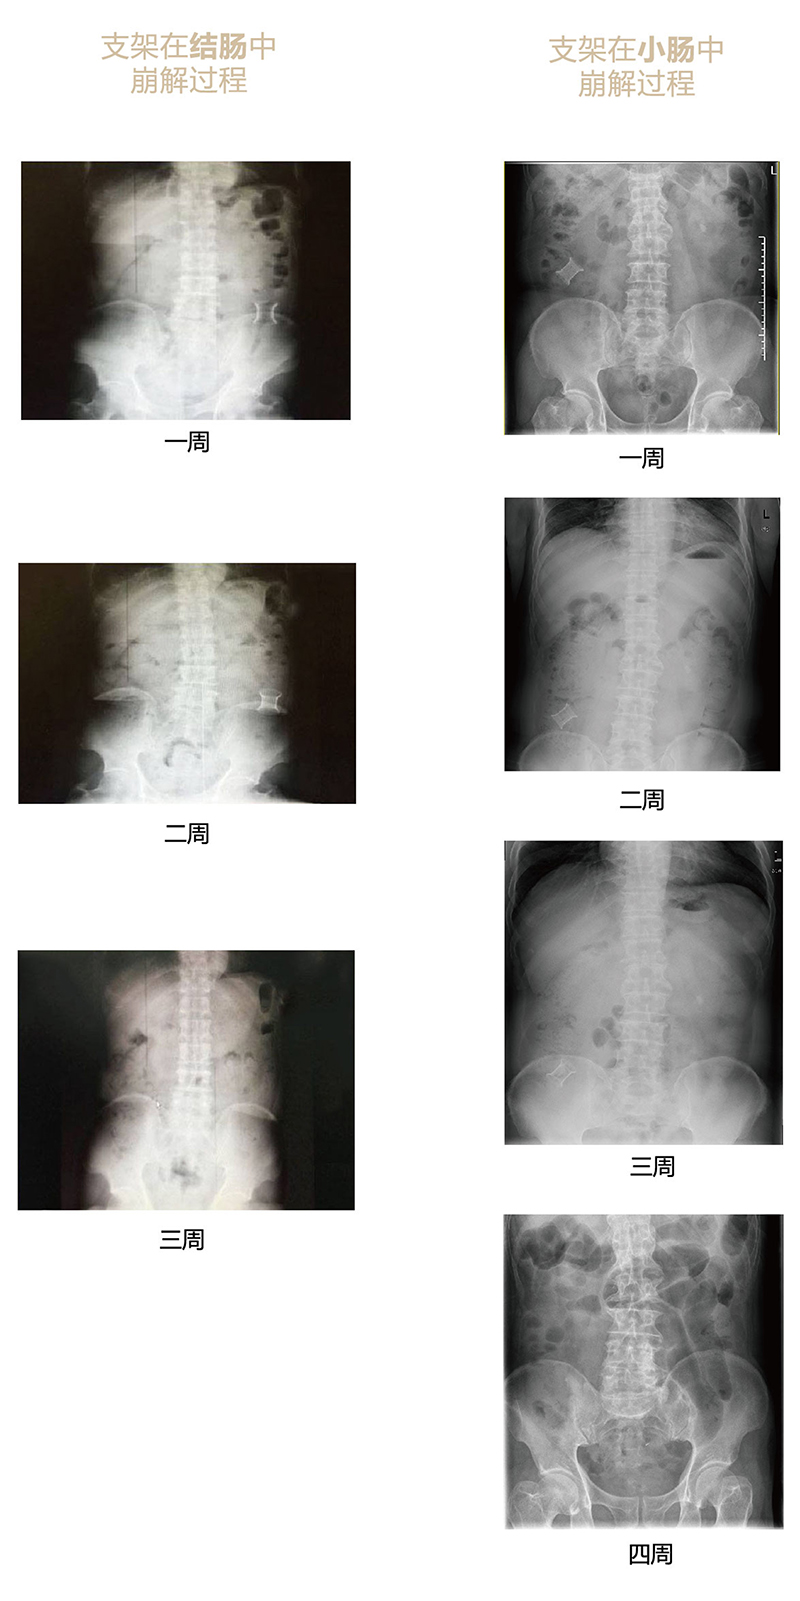

“可崩解腸道吻合器”由聚乙醇酸(PGA)與硫酸鋇按重量比7:1混合注塑制成,在X線下顯影,可動(dòng)態(tài)追蹤可崩解腸道吻合器(支架)在腸道內(nèi)崩解過程。

為解決該問題,蔡秀軍教授在“支架法空腔臟器吻合技術(shù)”的理念基礎(chǔ)上,又發(fā)明了“蔡氏腸轉(zhuǎn)流術(shù)”,這是一種應(yīng)用“可崩解腸道吻合器HB型(可崩解腸轉(zhuǎn)流支架)”(發(fā)明專利號(hào):201910794214.3),的支架法腸道轉(zhuǎn)流術(shù),此創(chuàng)新術(shù)式既能保護(hù)低位吻合口,更避免了回納術(shù)??杀澜饽c轉(zhuǎn)流支架在直腸癌根治術(shù)中植入遠(yuǎn)端回腸,可確保完全阻斷腸腔,用腸造瘺管在轉(zhuǎn)流支架近端行腸造瘺,起到完全轉(zhuǎn)流的作用。腸轉(zhuǎn)流支架在二至三周內(nèi)逐漸崩解,并在四周內(nèi)完全排出體外,恢復(fù)腸道通暢后拔除造瘺管,避免了傳統(tǒng)造口回納的二次手術(shù)。該創(chuàng)新術(shù)式具有方法簡單、吻合時(shí)間短、人體內(nèi)無異物永久殘留、不破壞吻合口粘膜下血管,并能預(yù)防吻合口漏、可避免人工肛門留置及二次手術(shù)、治療周期可縮短至二至四周、患者生理心理創(chuàng)傷顯著減少。